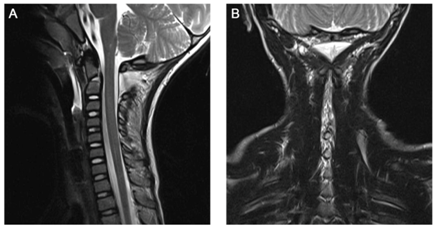

Examination showed a glascow coma score (GCS) of 15 with pupils equal, round, reactive to light and accommodation. He was responsive and alert on scene but couldn’t remember what has happened. The primary survey showed no disabilities or signs of head, chest, abdominal, pelvic or extremity injury. Both loss of head rotation and neck pain persisted. No abdominal damage aroused from sonographic assessment. We decided to perform a computed tomography (CT) of his head and neck to rule out intracerebral bleeding and fractures. Standard and 3D reconstructions revealed an atlanto-axial dislocation with a displacement of the atlas >5mm, a fracture of the odontoid process with a ventral axis tilt of 22° (Figure 1) and no signs of intracerebral bleeding. A following MRI scan Figure 2 showed ruptures of the interspinous ligaments from C2 to C6 with intact alar ligaments. The spinal cord showed no signs of damage. These findings lead to the diagnosis of an atlanto-axial-dislocation with synchondrotic fracture of the odontoid process in a neurologically intact 5-year-old boy.

Figure 2 Preoperative magnetic resonance imaging. A) Sagittal view of T2-weighted scan showing rupture and edema in the interspinous ligaments. B) Coronal view of T2-weighted scan with high-level signal along the interspinous ligaments and the C1-C2 facet joint on both sides.